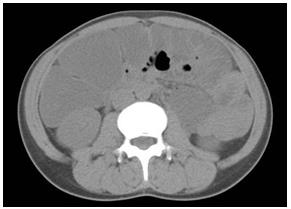

照片2:普通CT 照片

腹部全體發(fā)白。由于1.5L腸道準(zhǔn)備藥物停滯腸內(nèi),無法看見肝下緣,腎陰影,腸腰筋。看似腹水。橫結(jié)腸中有少量氣體。盆腔正中存在硬便和裂縫狀氣體。

照片3:腹部CT 照片,軸向圖像,上腹部

腸道內(nèi)堆積腸道準(zhǔn)備藥物明顯。腎臟前為升結(jié)腸,當(dāng)中是橫結(jié)腸。